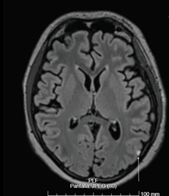

Resonancia magnética (RM) cerebral y de neuroeje: En el cráneo se observa captación leptomeníngea en surcos occipito-laterales izquierdos (Figura 2). En neuroeje se observa alteración de señal con captación de los somas toracolumbares y de los arcos costales como alteración de la hematopoyesis probablemente en el contexto de recaída tumoral. Además, se aprecia desde T11 hasta región sacra S1 proceso infiltrativo extramedular intrarraquídeo. Hallazgos neurorradiológicos compatibles con meningitis carcinomatosa e infiltración intraaxial extramedular intrarraquídeo de origen neoplásico.

Figura 2 Resonancia magnética cerebral en secuencia FLAIR, corte axial. Captación hiperintensa a nivel leptomeníngeo en surcos occipito-laterales izquierdos.